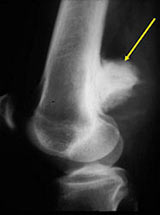

- Lobulated and ossified exophytic mass (cauliflower-like) adjacent to the cortex; attached to metaphyseal cortex via a broad base

- Centrally, the tumor is radiodense (demonstrates ossification)

- Peripherally there may be small radiolucies that represent low grade cartilaginous lobules, fibrous tissue or fat

- The underlying cortex may be thickened

- There is no periosteal reaction since the tumor comes from the outer layer of the periosteum and therefore does not elevate the periosteum.